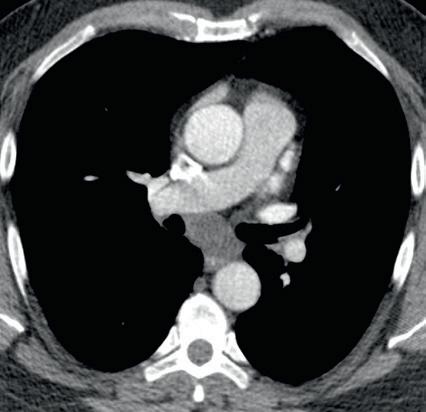

Most DECT datasets can be used to generate additional virtual monoenergetic images (typically between 40 and 60 keV [kilo electron volts]) that have high-contrast enhancement because they are close to the k-edge of the iodine. To minimize contrast streak artifacts and image noise in larger patients, higher keV images ( >70 keV) may be necessary. Iodine or pulmonary blood volume images represent material decomposition images (obtained from subtracting water from contrast-enhanced DECT images) that provide information on distribution of iodine in the lungs or remainder of the chest depending on the selected settings. The absolute iodine concentration expressed as milligrams per milliliter can be calculated from pulmonary blood volume images (Fig. 1.10). One can also generate water or virtual noncontrast images from contrast-enhanced

DECT by subtracting iodine from the image datasets to differentiate calcium, hemorrhage, or high-protein content from iodinated contrast (Fig. 1.11). The DECT technique also allows generation of higher keV images, which can help reduce artifacts with metallic implants or prostheses (Fig. 1.12).

FIGURE 1.11 Virtual noncontrast image. A soft tissue density mass is seen in the subcarinal region on the 140-kV image (A). On the virtual noncontrast (VNC) image (B), after iodine substraction, there is no change in the density of the subcarinal mass, and therefore there is no evidence for enhancement. This mass is consistent with a nonenhancing bronchogenic cyst.